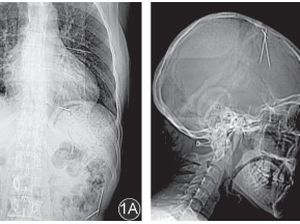

Foto Rontgen Ini Ungkap Temuan Jarum Misterius di Tubuh Pasien, Masuk Lewat Mana?

Dokter menemukan jarum besi misterius di rongga dada, perut, dan kepala seorang pasien wanita. Tak pernah diketahui, jarum besi tersebut berasal.